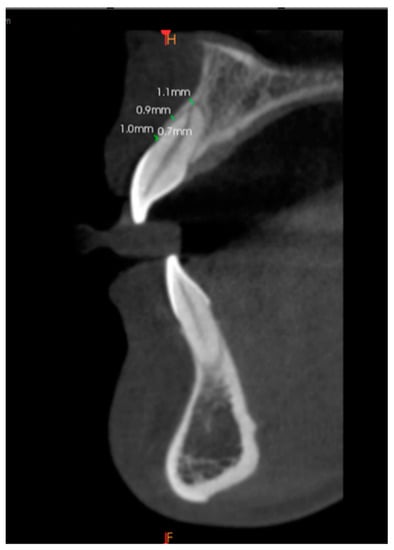

2.3. Scan Measurements

Alveolar Bone Thickness Measurement